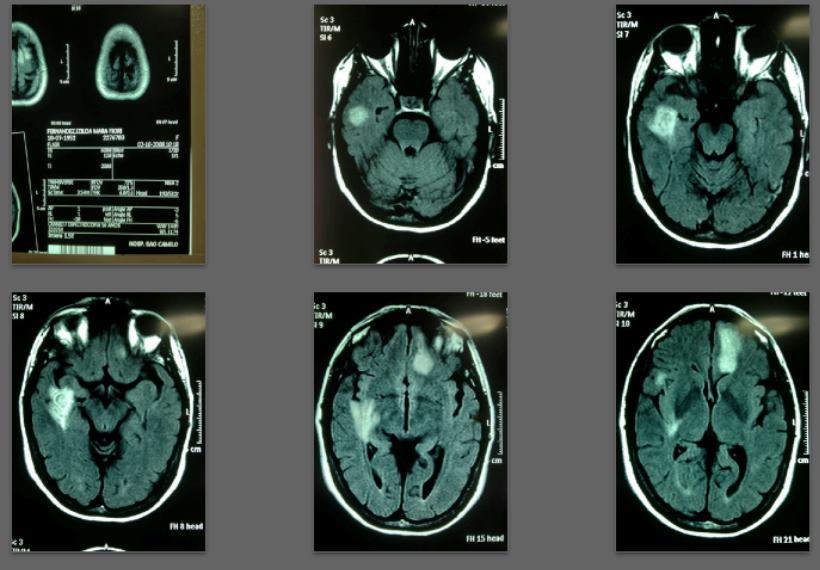

Before/after MRI images for one of 1,000+ patients of Dr. Coimbra

2008 Convulsive seizures Diagnosis: Balo’s concentric hemiparesis

Starting daily dose 25,000 IU; increased in stages to 80,000 IU on October 28, 2010. Asymptomatic since 2010.

2008 MRI

2013 MRI